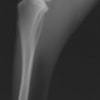

術前TPA計測

術後TPA計測

手術前TPA 28.4° が術後TPA 11.7° に矯正されました。